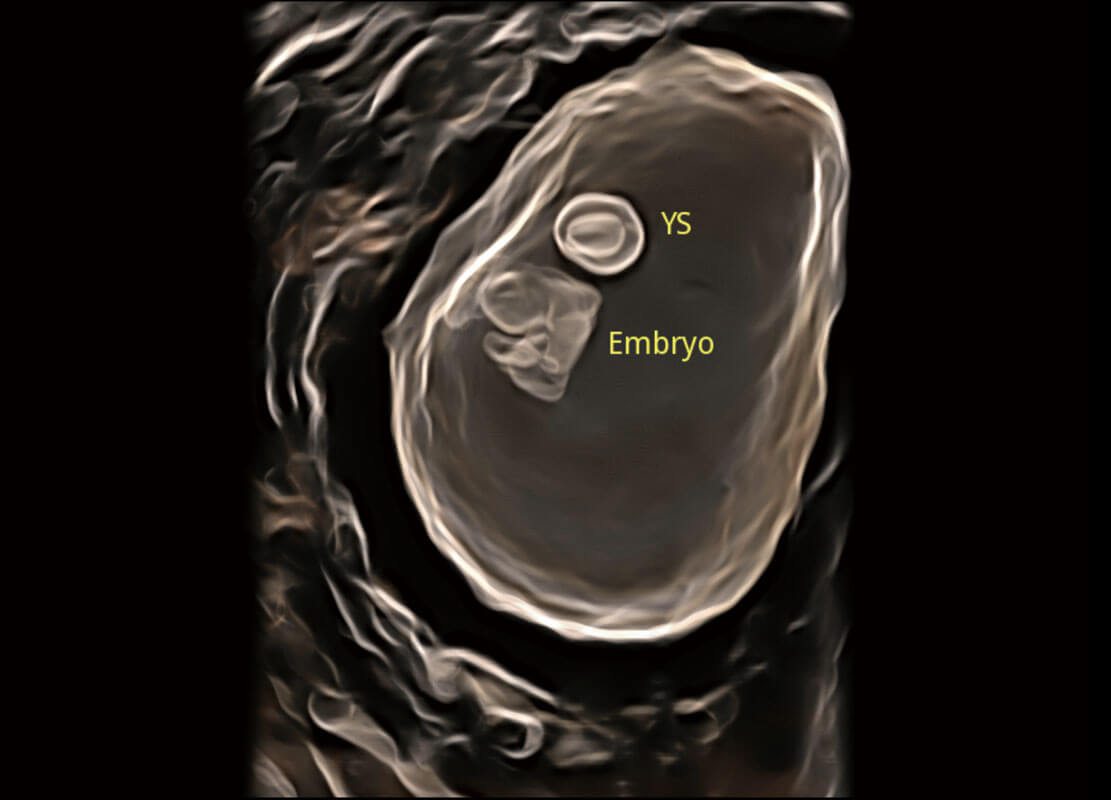

P60在胎儿早孕期超声筛查中为您带来优异的图像质量。

早孕-胎心

高分辨率容积成像-早孕胎儿

胎儿体循环

光影成像-孕囊